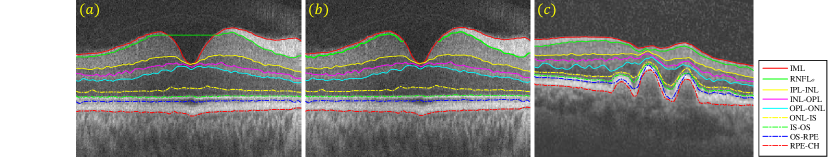

In this section, we will provide an overview of the state-of-the-art methods (i.e. parallel double snakes [14], Chiu’s method [15], OCTRIMA3D [29, 30], Dufour’s method [27]) that will be compared with our proposed GDM in Section 3. For a complete review on the subject, we refer the reader to [39]. Among the four methods reviewed, the first two can only segment B-scans, while the latter two are able to extract retinal surfaces from volumetric OCT data. We note that the term ‘surface’ refers to a set of voxels that fall on the interface between two adjacent retinal layer structures. The retinal layer boundaries to be delineated are shown in Figure 2.

where the image energy ( is the image gradient operator) attracts the parametric curve towards one of retinal borders of the input B-scan , whilst handles curve which is parallel to . The internal energy imposes both first and second order smooth regularities on the central curve , with and respectively controlling the tension and rigidity of this curve. is a parallelism constraint imposed on and . Nine retinal borders have been delineated by the method, i.e., ILM, RNFLo, IPL-INL, INL-OPL, OPL-ONL, ONL-IS, IS-OS, OS-RPE and RPE-CH.

In this section, we propose a novel framework using the geodesic distance to detect from OCT images nine retinal layer boundaries defined in Figure 2 and Table 1. As the proposed methodology applies equally to both 2D and 3D segmentation, we will illustrate the approach for 2D segmentation here, as the steps would be the same for 3D segmentation. Numerical implementation of the approach is given in Appendix.

The retinal layers of OCT images are normally near horizontal. The gradient in the vertical direction thus can be considered as a good candidate for computing weight in (3.1). For instance, each of the two prominent boundaries, e.g. ILM () and IS-OS () in Figure 3 (a) and (e), is at the border of a dark layer above a bright layer. As a result, pixels in the region around the two boundaries will have high gradient values, as shown in Figure 3 (b) and (f). As the retinal layers at each side of the boundary are either transiting from dark to bright or bright to dark, the non-negative weight function in this paper is defined based on intensity variation as follows